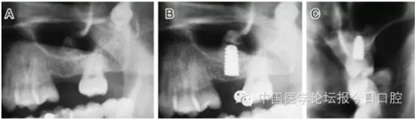

病例3 有骨間隔(圖5)

圖5